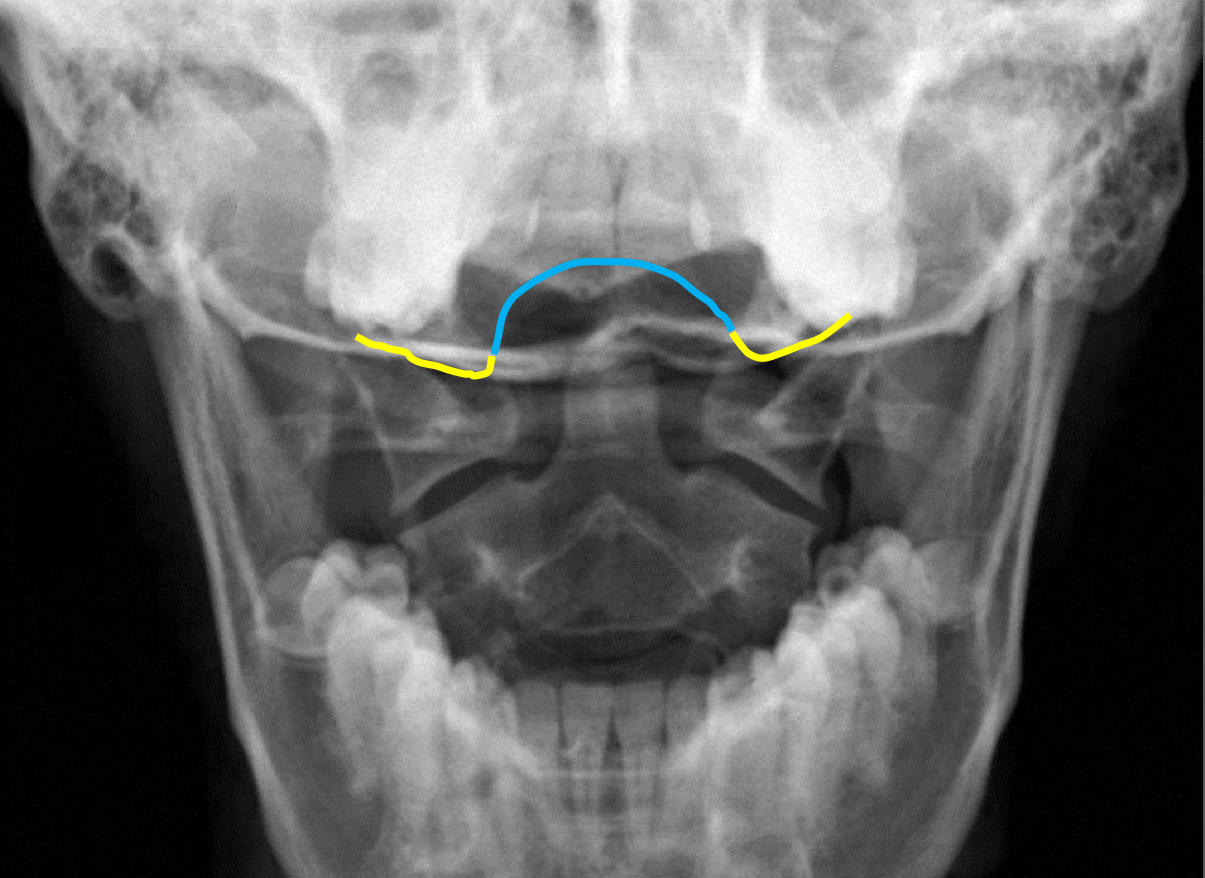

What view is this?

APOM

What is this - Yellow?

Occipital Condyles

What is this - blue?

Foramen Magnum

What is this?

C1 TVP/Lateral Mass Junction

What is this?

Odontoid Process

What is this?

C2 Spinous Process

What is this?

C2 Pedicle Shadows